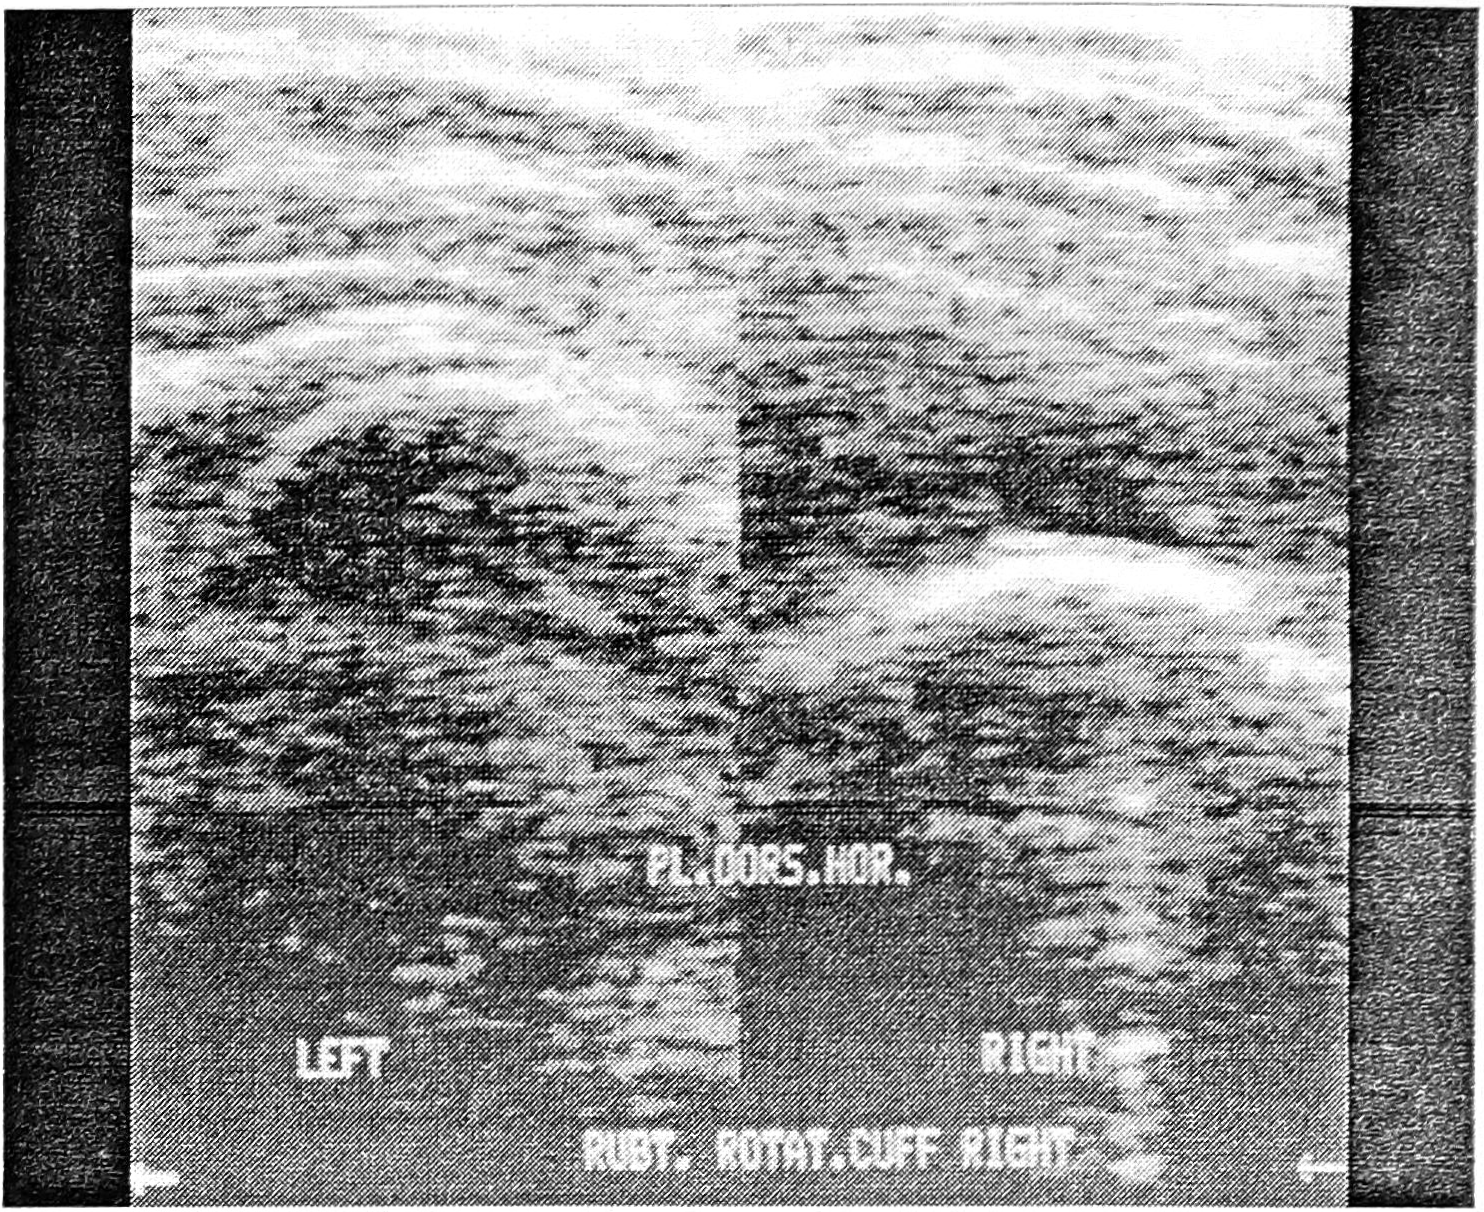

Повреждение мышечно-связочной (ротаторной) манжетки является достаточно частой причиной боли в плече. УЗИ плечевого сустава позволяет с высокой точностью определить структурно-функциональное состояние наружных ротаторов плеча как в норме, так и при различных патологических процессах. Исследование сухожилия подостной мышцы (наиболее вероятная область повреждения) в положении гиперэкстензии плеча рекомендуется проводить в вентральной горизонтальной и вентральной вертикальной проекциях.

1) отсутствие эхосигнала манжетки при ее отрыве от большого бугра и ретракции подакромиальный отросток; в этом случае дельтовидная мышца прилежит к головке плечевой кости (рис. 1). Диагностическая значимость этого признака приближается к 100%;

Рис. 1. Разрыв ротаторной манжетки правого плеча.